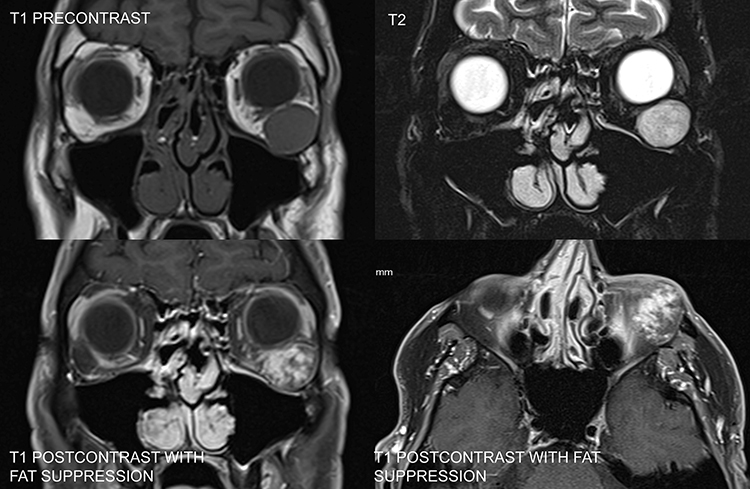

| Dermoid or epidermoid cyst | A well-defined lesion that may mold to the bone of the orbital walls. On occasion, bony erosion is noted with the extension of the lesion intracranially or into the temporalis fossa (dumbbell dermoid). | Hypointense to fat, but usually hyperintense to vitreous. Only capsule enhances with gadolinium. Signal may increase if a large amount of viscous mucus (high protein-to-water ratio) is present within the lesionan uncommon finding for most orbital masses and helpful in distinguishing this lesion from others | Iso- or hypointense to fat |

| Hemangioma of infancy | Irregular, contrast enhancing | Well defined, hypointense to fat, hyperintense to muscle | Hyperintense to fat and muscle |

| Rhabdomyosarcoma | An irregular, well-defined lesion with possible bone destruction | Isointense to muscle | Hyperintense to muscle |

| Metastatic neuroblastoma | Poorly defined mass with bony destruction | | |

| Lymphangioma | Nonencapsulated irregular mass, crabgrass of the orbit | Cystic, possibly multiloculated, heterogeneous mass. Hypointense to fat, hyperintense to muscle, diffuse enhancement. May show signal of either acute or subacute hemorrhage (hyperintensity on T1) | Markedly hyperintense to fat and muscle |

| Optic nerve glioma | Fusiform enlargement of the optic nerve | Tubular or fusiform mass, hypointense to gray matter | Homogeneous hyperintensity |

| Plexiform neurofibroma | Diffuse, irregular soft tissue mass, possible defect in orbital roof | Iso- or slightly hyperintense to muscle | Hyperintense to fat and muscle |

| Leukemia (granulocytic sarcoma) | Irregular mass with occasional bony erosion | | |

| Langerhans cell histiocytosis | Lytic defect, most commonly in superotemporal orbit or sphenoid wing | Isointense to muscle, good enhancement | |